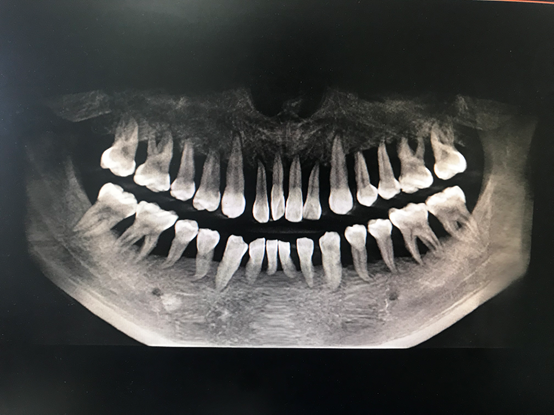

近日,25歲的小周碰到了一個大難題,他的牙“出問題了”,全口牙齒無法咀嚼,除了流食以外什么也不能吃。杭州師范大學附屬醫(yī)院牙周病診療中心醫(yī)生發(fā)現(xiàn),小周的牙齒情況類似于80歲的老太太,全口牙齒幾乎都是松動無法行使咀嚼功能。這意味著小周口內牙齒幾乎都要拔除,全口牙沒有幾個能保留。

“我從醫(yī)這么多年也是第一次見到如此嚴重的牙周炎患者?!苯釉\醫(yī)生周矗說,從小周的口腔檢查中發(fā)現(xiàn),他的全口牙齒都有牙齦的膿腫,伴有嚴重的骨頭萎縮以及吸收,所有牙齒幾乎都是3度松動,并且口腔異味特別嚴重,牙齒上附著大量牙結石及食物軟垢。

“如今要先通過基礎調節(jié)解決小周全口牙齦膿腫的問題。”周矗表示,待炎癥控制后再開始拔除無法保留的牙齒及多個缺失牙的種植修復。經過2周的調節(jié),小周的全口牙齒口腔環(huán)境已經有了的改良。